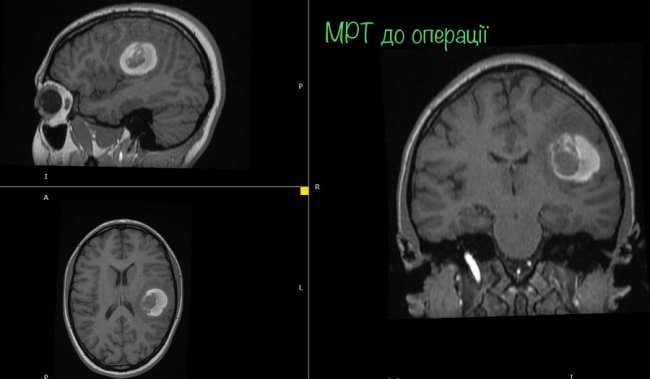

На МРТ виявили пухлину головного мозку з крововиливом в лівій домінуючій (важливішій) півкулі, в якій, власне, окрім центрів, які рухають кінцівками однієї половини тіла, розташований дуже важливий центр мови.

"Саме тому єдиний варіант врятувати здатність розмовляти можна тільки провівши таке втручання у свідомості. Тобто під час операції на головному мозку потрібно розбудити пацієнта. Потрібно не просто розбудити, а ще й знайти центр мови, який у кожного з нас розташований по-своєму, а тоді видалити пухлину за короткий час пробудження (близько години). І після цього знову ввести в наркоз", - розповідає Ловга.